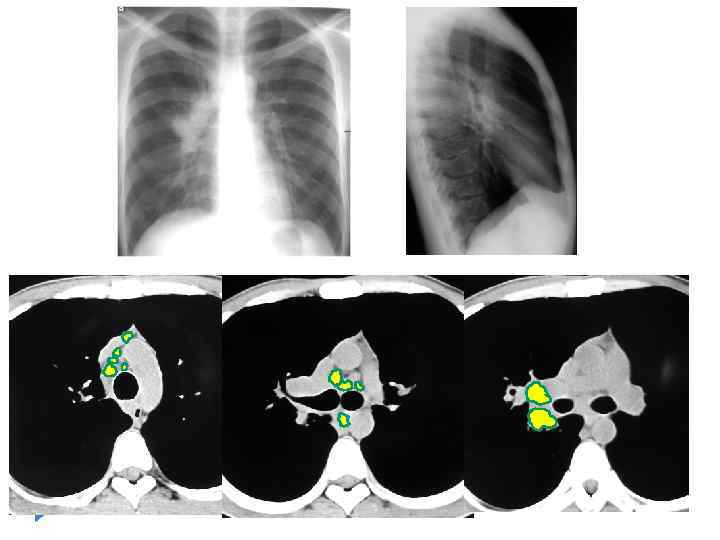

Рентгенологические признаки при туморозной форме ТВГЛУ Расширение тени средостения или объёмное увеличение корня лёгкого Контуры чёткие полицикличные Одностороннее Ассиметричное двустороннее с преимущественным вовлечением в процесс бронхопульмональных групп.

Рентгенологические признаки при туморозной форме ТВГЛУ Расширение тени средостения или объёмное увеличение корня лёгкого Контуры чёткие полицикличные Одностороннее Ассиметричное двустороннее с преимущественным вовлечением в процесс бронхопульмональных групп.

Туморозная форма ТВГЛУ

Туморозная форма ТВГЛУ